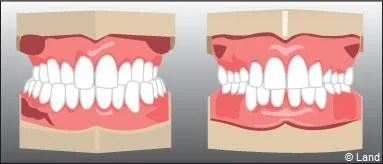

Les traitements précoces sont réalisés avant l’évolution de l’ensemble des dents définitives:

De plus, il est opportun de corriger très tôt certaines malpositions. Les appareils généralement utilisés sont amovibles avec une armature en résine, mais peuvent aussi être fixes à l’aide de bagues sur les premières molaires définitives.. Suivant leurs conceptions et la manière dont ils sont portés, ils auront une action sur la position des dents mais aussi sur la croissance.